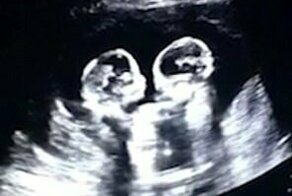

Появление на свет двойняшек Кэти и Эми врачи приравняли к выигрышу в лотерею. Вопреки врачебным прогнозам и законам природы, они родились с разницей в 87 дней. В этом году они пошли в первый класс!

В этом году близняшки Кэти и Эми, родившиеся в 2012 году с разницей в 87 дней, вместе пошли в первый класс. По врачебным прогнозам, им было не суждено появиться на свет, но все каким-то чудом сложилось благоприятно.